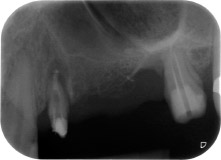

Une patiente de 58 ans se plaignait de douleurs et d'une mobilité accrue de la dent pilier 24 de son bridge. Présence d'une inflammation parodontale avec formation de poches de 7 mm de profondeur dans le sens mésiobuccal et de plus de 12 mm dans le sens distal, ainsi que d'une atteinte de la furcation au troisième degré. La radiographie a par ailleurs révélé une lésion parodontale étendue autour de la région apicale de la dent 24 ayant préalablement reçu un traitement endodontique (alio loco) (Fig. 1).

À la racine de la dent, il manquait la totalité de l'os vestibulaire et distal. L'attache était essentiellement limitée à la racine palatine, venant ainsi confirmer le pronostic défavorable initial. La dent 27 présentait également une attache horizontale réduite et une raréfaction apicale minime (cf. Fig. 1), sans symptômes cliniques.